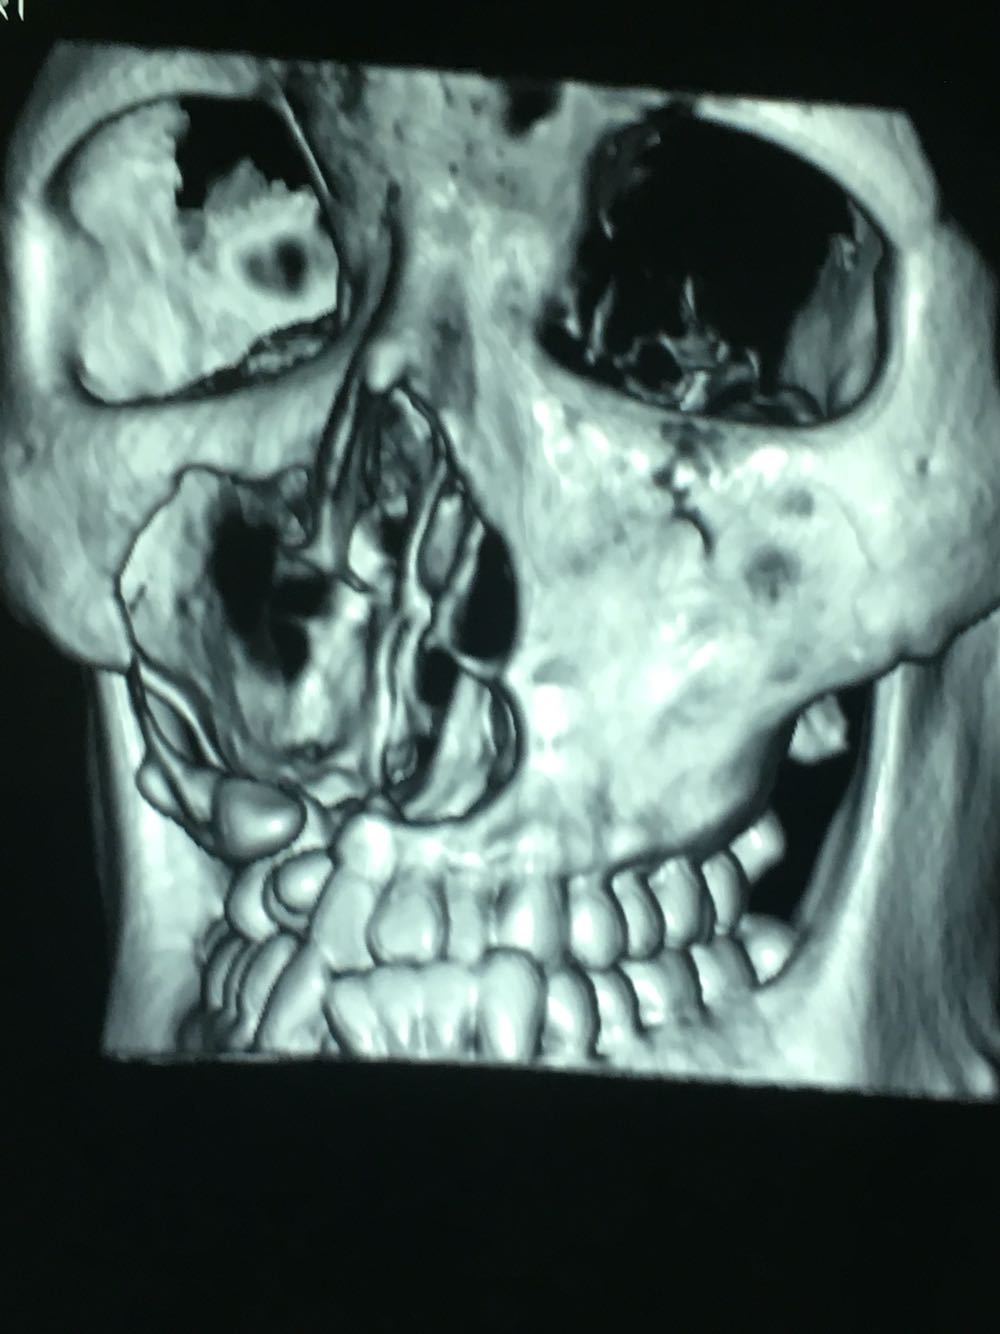

查体:面部明显不对称,右上颌膨隆明显,右鼻翼抬高,眶下区无麻木感,眼球运动自如,13牙齿缺如,16-22牙齿唇侧前庭肿胀,中央扪及波动感,边缘乒乓感,相关牙齿1度松动。 辅查:穿刺,抽得淡黄色液体,全景及CT,上颌骨囊肿,右侧上颌骨骨质大部分破坏

诊断:右上颌骨囊肿,13埋伏阻生。 治疗:开窗减压,拔除13阻生牙齿